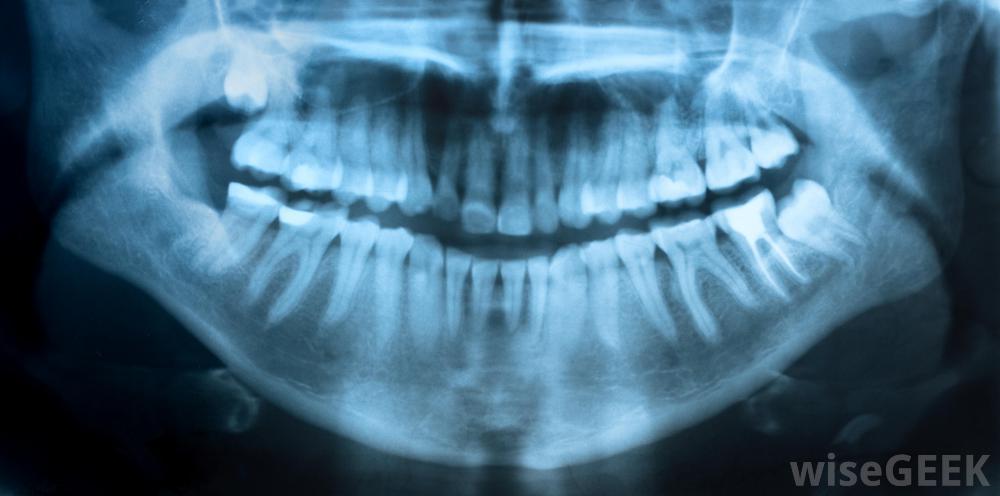

如果牙龈痛是由于牙齿问题引起的,可能需要用牙科x光检查,溃疡和口腔溃疡是造成这种情况的两个常见原因,这两个原因都与口腔卫生不良有关,这些都是口腔开放性脓肿细菌滋生和繁殖,破坏感染源周围健康的牙龈组织。日常口腔卫生方案应包括在单个牙齿之间使用牙线和使用维护良好的牙刷使用含氟牙膏刷牙。这些活动应每天进行两次,并且根据牙医的建议,一整天都要重复。过度刷牙和用硬牙刷刷牙太用力也应该避免,因为这些活动也会导致口腔干燥和去除有益牙釉质而导致牙龈疼痛

定期的口腔卫生,如牙线清洁,将有助于治疗牙龈疼痛牙龈酸痛也可能是由于牙齿感染、怀孕或维生素缺乏引起的。如果增加日常口腔护理和消毒洗漱,在一周内仍不能解决问题,病人应该去看牙医,对牙龈疼痛采取不同的治疗方法。有些脓肿可能发生在牙齿和牙龈之间的小间隙中,并可能向下延伸到牙根,形成一个紧密的感染球。这种类型的脓肿只能在牙科x光片上看到,并且需要专业的引流和一个疗程的抗生素来对抗任何新感染的形成。